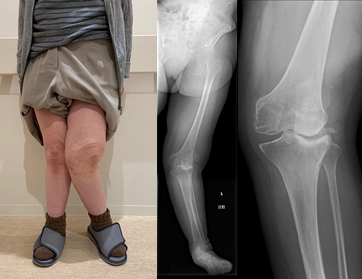

高度X脚

脛骨の近位部を骨切りし、O脚に変形した下肢を軽度X脚に矯正し、荷重による負担を膝外側に移動することによって、膝内側の痛みを緩和する方法です。変形の程度によって開大式と閉鎖式骨切り術を使い分けております。

人工膝関節単顆置換術 (unicompartmental knee arthroplasty: UKA)

膝関節の内側もしくは外側のみの単顆型の変形や骨壊死症に適応があります。片側のみの人工関節置換術であることから、手術侵襲が少なく、術早期から除痛が得られ、歩行が可能となります。